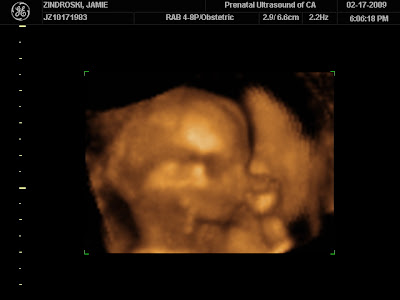

We have a DVD of Bambino now from our ultrasound and 'it' has grown so much! Bambino's always moving around, sucking its thumb, has long little fingers (like I did), a button nose, and puckered lips. The 3D ultra sound is so cool because you can actually see all its little features! What a keepsake! If we can figure out how to upload it we will post it on here as well! Stay tuned next week when we try find out AGAIN!!!

As of Monday we are 16 weeks along and doing great! We have kept very busy lately between the move, working, and racing, but soon it will mellow out for a few weeks! I am feeling much better as the preggie symptoms subside, just a bit tired still. We got to hear Bambino's heartbeat a lot lately between all the Dr's visits and we even got to see him again! We were supposed to officially find out the gender yesterday, but 'it' was being a little stubborn haha and the umbilical cord was between its legs- hiding any goods from us. So we will try again next Tuesday- stay tuned!